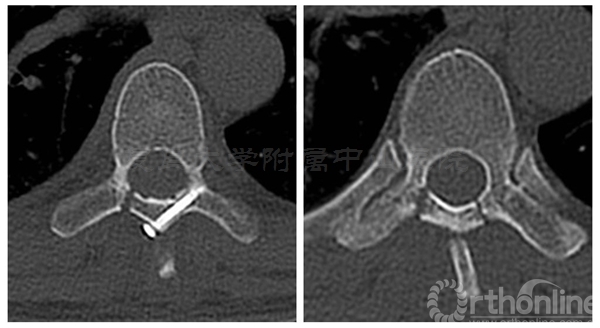

术前三维CT:T7/8水平可见椎管内占位

术中椎板截骨行肿瘤切除后,椎板回植术,回植椎板采用空心螺钉固定

术后肌力恢复至4+级,无脑脊液漏,X线片及CT平扫显示椎板回植位置满意,空心钉固定牢靠。术后病理诊断为脊膜瘤伴细胞丰富

术后三个月患者腰背痛完全缓解,肌力已恢复至5级,下肢麻木感消失。CT显示:椎板截骨面已骨性愈合,无移位,椎管容积与术前无明显差异